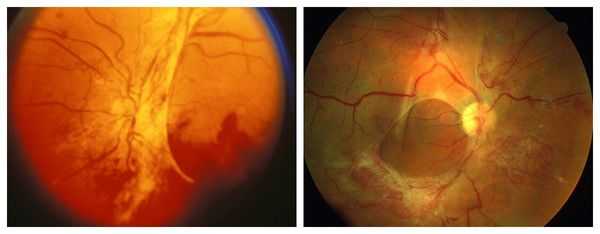

При благоприятных исходах РН основным видом осложнений было развитие и прогрессирование периферических ретинальных дистрофий (26 глаз) по типу «решетки», «следа улитки», разрывов сетчатки, ретиношизиса (рис. 4). В большинстве случаев развитие этого вида осложнений произошло на глазах с РН II степени (19 из 26 глаз; 73%).

Рис. 4. Периферическая ретинальная дистрофия по типу «следа улитки» на глазу со II степенью рубцовой РН.

Развитие и прогрессирование ретинальных дистрофий привело к возникновению отслойки сетчатки на 13 глазах с II—IV степенью РН у детей в возрасте от 9 до 17 лет (в среднем в 14,1 года). При II степени РН отслойка сетчатки носила регматогенный характер (5 глаз), а при III и IV степени — регматогенный и тракционно-регматогенный характер (8 глаз), что потребовало комбинированных хирургических вмешательств (рис. 5).

Рис. 5. Поздняя субтотальная отслойка сетчатки регматогенного характера на глазу с РН II степени и частичной атрофией зрительного нерва.